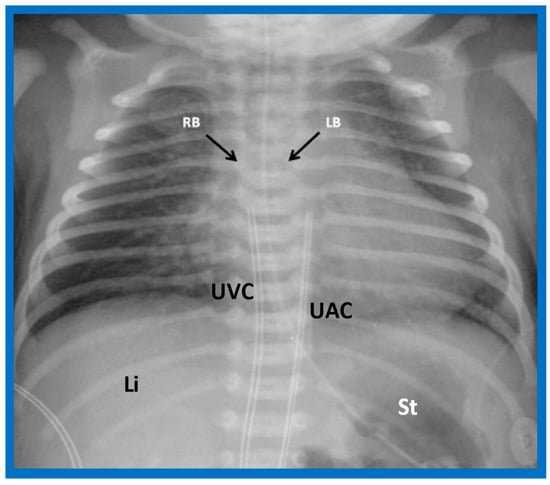

In typical patients with situs solitus, the bronchus on the right side is short and wide and descends somewhat steeply, whereas the bronchus on the left side is longer and narrower than the right bronchus and descends rather horizontally (Figure 22A and Figure 23). On the contrary, in patients with situs inversus, the tracheobronchial tree configuration is inverted (Figure 22B and Figure 24) [2,3,4,5]. The tracheobronchial tree pattern seems more correct than the above two approaches to identifying the atrial situs [2,26,27]. Tomography has been used in the past [27] to more accurately determine bronchial morphology and measure the bronchial lengths but is not routinely used at the present time because of increased radiation exposure associated with tomography and the availability of other imaging studies.

Figure 23. A chest roentgenogram of a patient with situs solitus demonstrating a wide and short right bronchus (RB) which descends somewhat steeply, whereas the left-sided bronchus (LB) is narrow and long and traverses horizontally. The liver (Li) is seen on the right side, and the stomach (St) bubble is seen on the left side, consistent with situs solitus. Mild cardiac enlargement and increased lung vascular patterns are also seen. UAC indicates an umbilical arterial catheter, and UVC points to the catheter in the umbilical vein. Modified from reference [4].